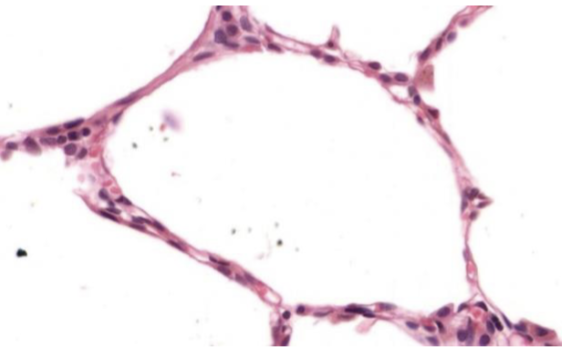

plano

Número de estratos

simple

Forma de sus células

plano

Número de estratos

simple

Indique órgano o sistema que posee este epitelio

alveolo